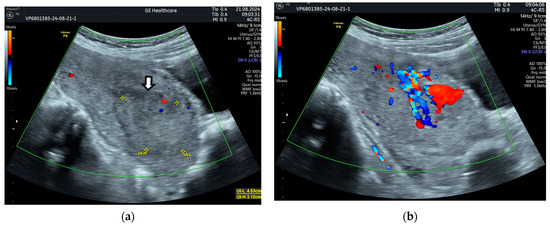

2. Case Presentation